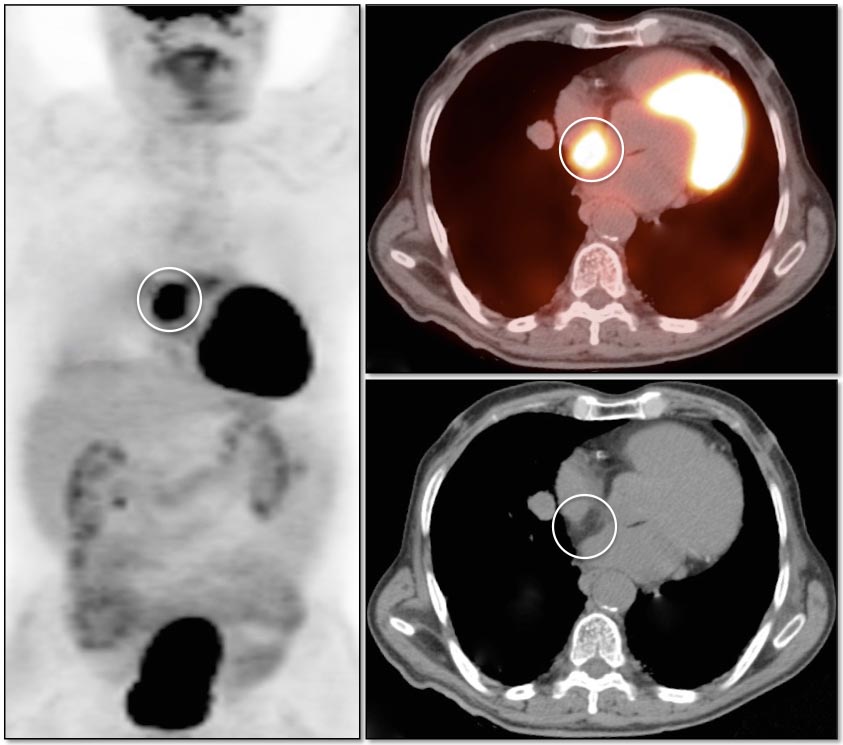

Please note that while the above cancers sometimes demonstrate poor metabolic activity, they can also be quite FDG-avid. [Fig. 2]